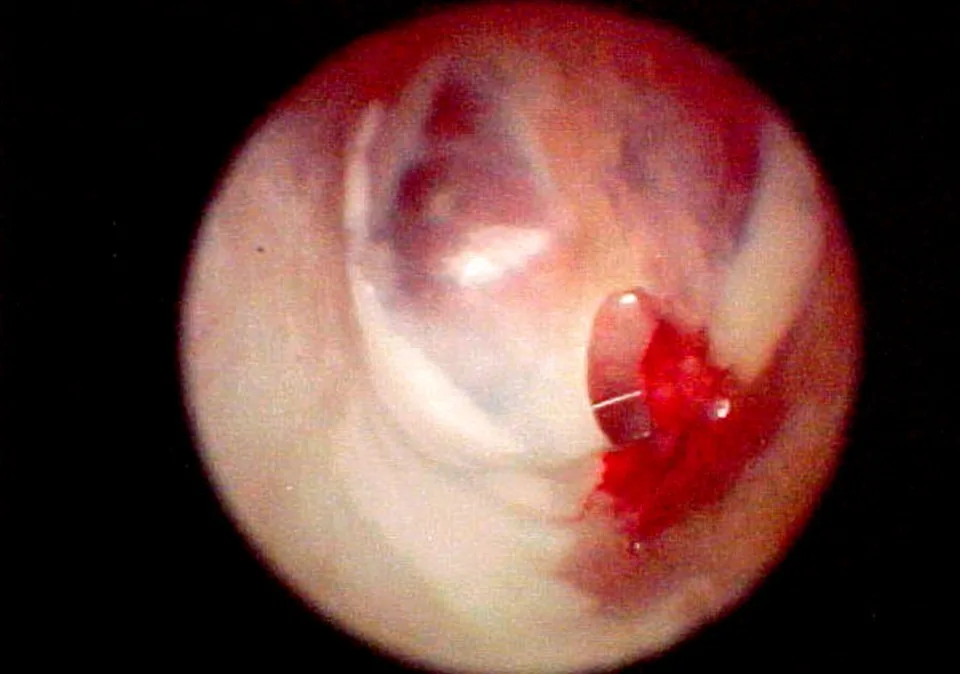

Bulging eardrum identified on otic examination (Figure 1)

FIGURE 1 Middle ear exudates fill tympanic bulla, putting painful pressure on the eardrum and causing it to bulge outward.